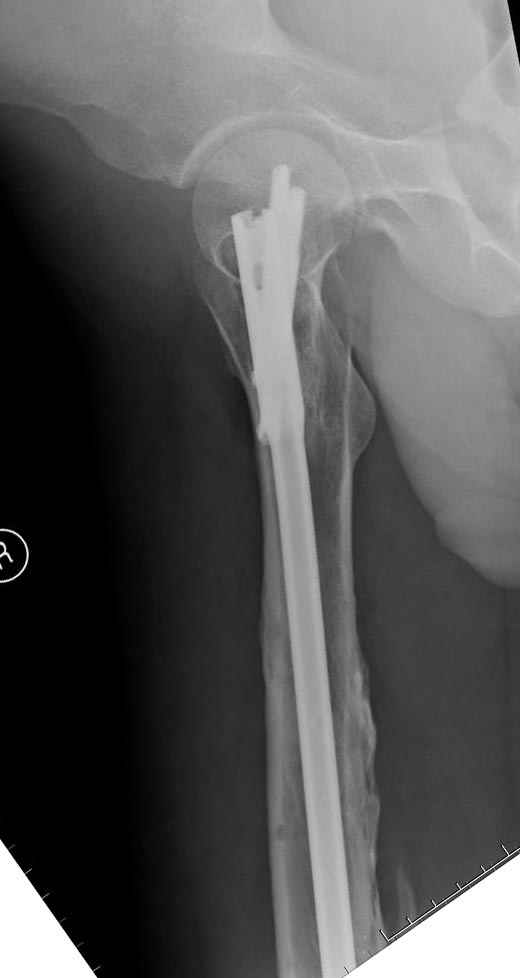

Мы не дождались “Happy End”, у больного IQ в пределах 70%, через 6 месяцев вернулся после небольшой травмы, споткнувшись получил перелом

того же бедра (рис №7).

На следующий день произвели интрамедуллярный остеосинтез: этапы во время операции (рис №8, №9)

и последующих снимках (рис №10, 11, 12, 13) перелом сростается и передвигается с полной нагрузкой.

При обзоре причин перелома, на снимке №2 обнаружили, что один из стержней аппарата наружной фиксации проходил только через передний кортекальный слой, что создало стрессовую зону на бедре и в результате перелом из-за незначительной травмы.